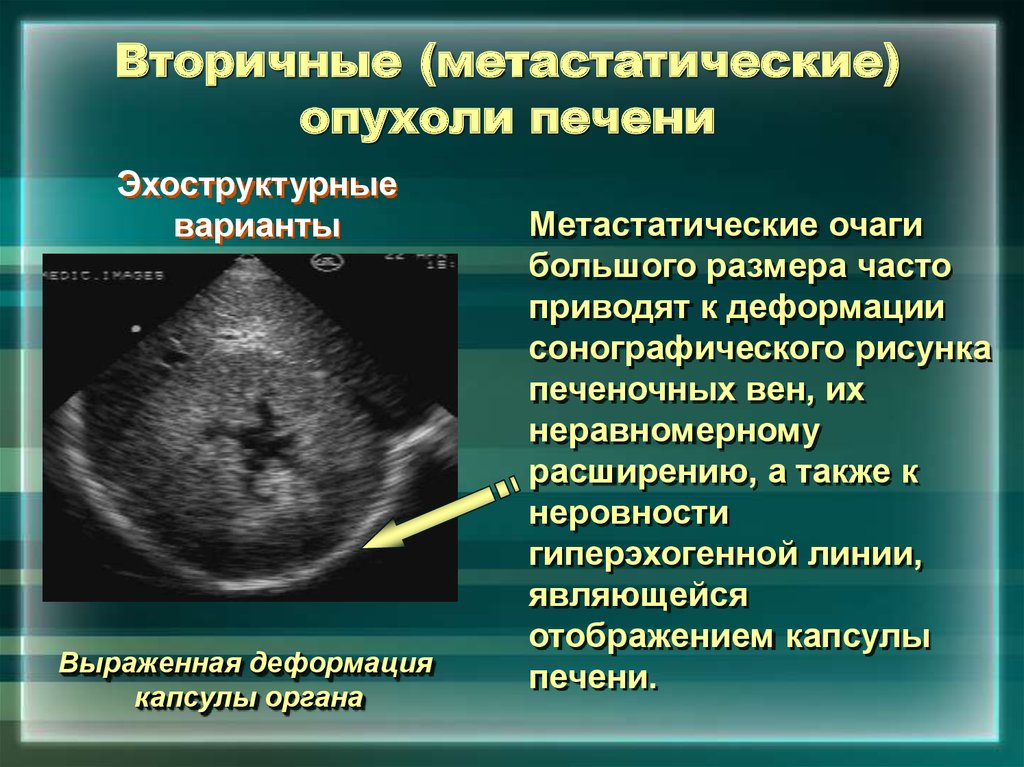

Метастатические поражения печени в ультразвуковом изображении характеризуются